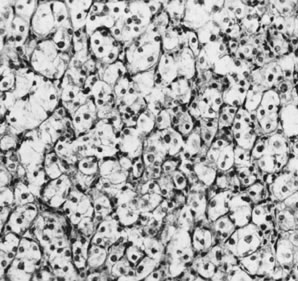

On microscopic examination, the granulosa cell tumor can be divided into two major subtypes, adult form and juvenile form, which differ strikingly in their patterns and cytologic features. The adult granulosa cell tumor is occasionally composed almost entirely of granulosa cells, with few or no accompanying thecal or fibroblastic elements, but more often the latter are present in some amount and may be substantial. The granulosa cell component of the tumor has a variety of patterns. The well-differentiated form most commonly has a microfollicular (Fig. 2), trabecular (Fig. 3), or insular pattern, or a combination of the three. Rarely, the pattern is macrofollicular, with the tumor composed of large follicles resembling normally developing follicles. Less well-differentiated tumors typically have a diffuse or sarcomatoid pattern, characterized by a sea of cells with little or no intervening stroma (Fig. 4); this type of tumor is particularly apt to rupture. Sometimes a watered-silk or zigzag (gyriform) pattern is seen. The stromal element of the tumor may consist of fibroblasts that have laid down considerable collagen, as well as cells that resemble theca externa, theca interna, or theca lutein cells.

Fig. 2. Granulosa cell tumor, microfollicular pattern with Call-Exner bodies (magnification, ×290).(Scully RE, Morris JM: Functioning ovarian tumors. In Meigs JV, Sturgis SH [eds]: Progress in Gynecology, Vol 3. New York, Grune & Siralton, 1957, by permission.)